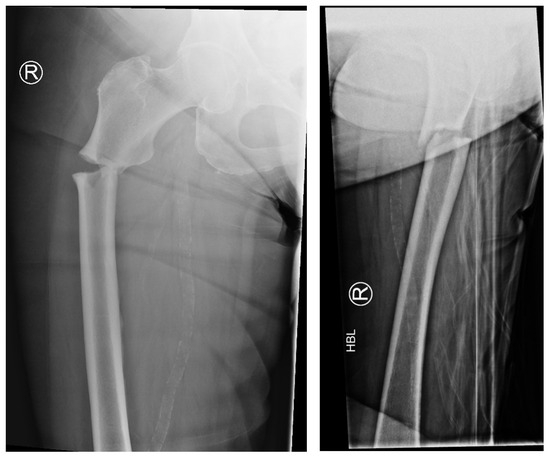

The following radiographs present the initial radiographs from the day of injury along with those obtained during the final OPD follow-up of the patient. The sequence presents radiographs demonstrating full radiological union (Scheme 1 and Scheme 2) and X-rays with no evidence of fracture healing at the final OPD follow-up (Scheme 3 and Scheme 4).

Scheme 3. X-ray of right femur AP view (left) and lateral view (right) of atypical subtrochanteric stress fracture—July 2022.

Jcm 14 02858 sch003

Scheme 4. X-ray of right femur AP view (left) and lateral view (right) of atypical subtrochanteric stress fracture—September 2024 (no features of healing).

Jcm 14 02858 sch004